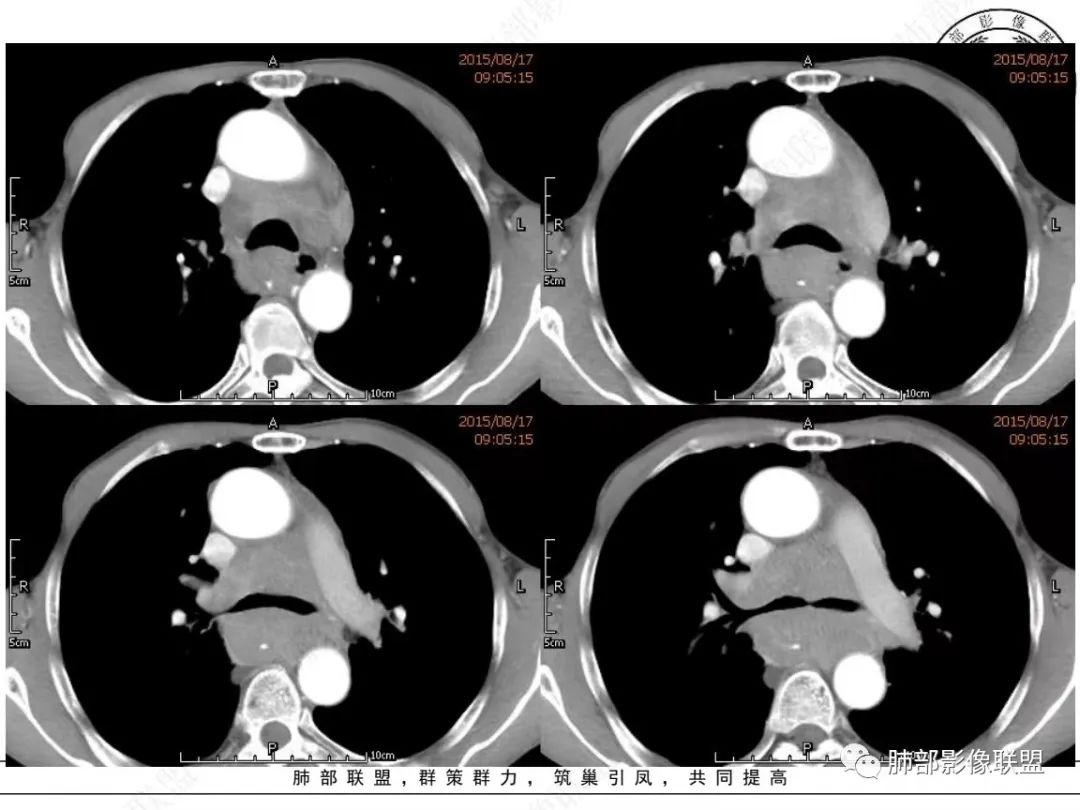

谢加平:纵隔内中后纵隔及右肺门淋巴结肿大,形成大肿块,整体密度均匀,并轻度强化,见“血管飘浮”征,包绕气管分叉及右主支气管及中间段支气管明显受压狭窄,并包埋右肺门血管束,无侵蚀破坏,右肺动脉后壁见压迹影,右肺下叶背段有阻塞性炎症,首选淋巴瘤,支气管超声内镜活检,明确诊断!

理由:四点,1、整个病灶位于纵隔中央后主,且以后纵隔为主,2、病灶内血管漂浮,3、肺内无原发灶,没找到“娘”。4、颌下淋巴结穿刺未找到小细胞癌。所以肯定先考虑淋巴瘤。

南边:

老年男性,颈部淋巴结而来,双侧对称,长期吸烟,双侧腋窝淋巴结肿大

,纵隔淋巴结肿大,特别是后纵隔,食道推移包绕,右肺门区支气管被包绕、受压狭窄。恶性应该没问题,问题是如何鉴别小细胞与淋巴瘤?

1、颈部、腋窝双侧淋巴结对称

2、右肺门区淋巴结肿大,但是没有沿支气管朝外延伸

3、食道没有梗阻

4、血管漂浮,走形自然

支持淋巴瘤